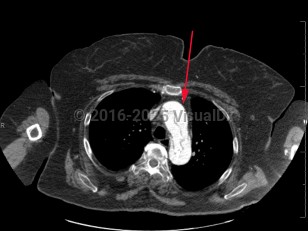

Aortic dissectionAortic dissection

PneumomediastinumPneumomediastinum